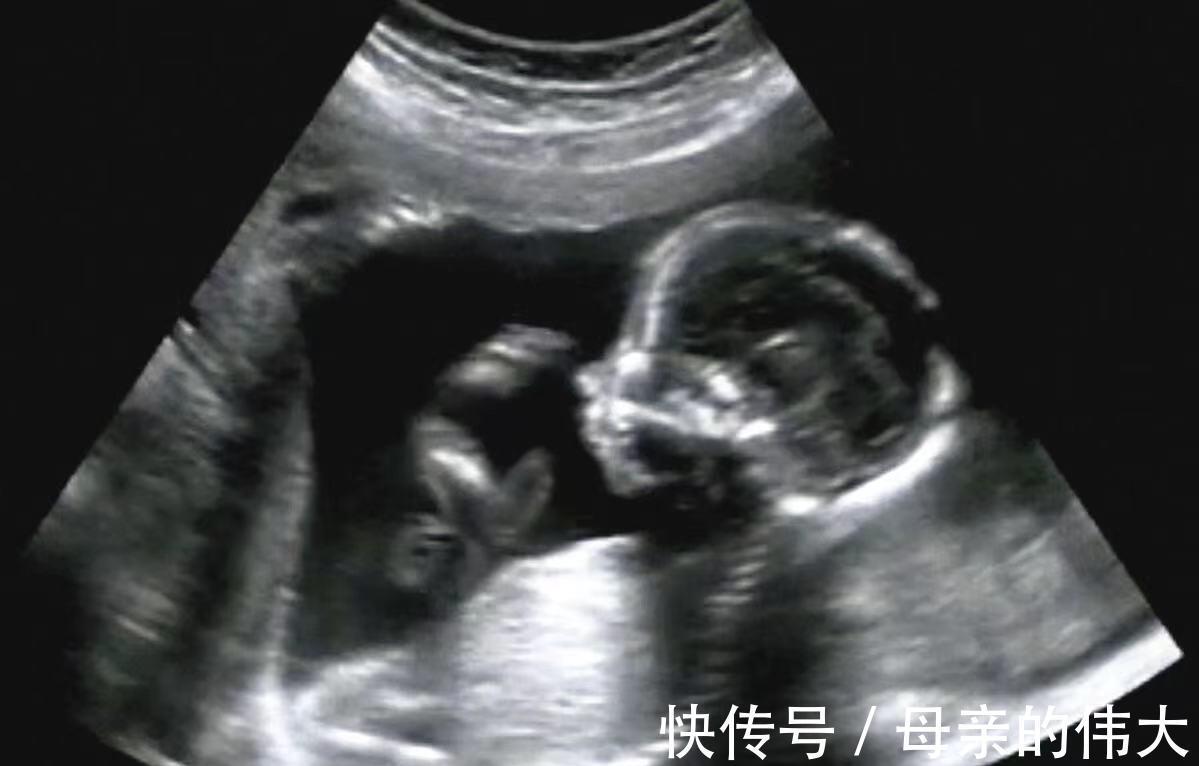

四维彩超是通过现代科技透过肚皮看到宝宝在肚子里的一些情况一般都可以看到宝宝的五官大概是什么样子如果你有做过四维彩超应该对这个过程很清楚。有的宝宝没几分钟就做完了但是有的宝宝费半天劲都没有拍到正脸难道是宝宝害羞不肯亮相吗

碰到调皮的宝宝宝妈就需要受累了需要多走动几圈或者跟宝宝做个互动才能够全部看清楚宝宝的情况。其实准备做四维彩超的时候想要保证顺利进行只需要提前做些准备就能够很快地做好。